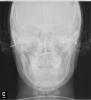

oxpod Опубликовано 10 мая, 2012 Автор Поделиться Опубликовано 10 мая, 2012 (изменено) Добавьте ТРГ к кейсу. Тактика лечения открытого прикуса: либо двучелюстная ортогнатия (хирургия) либо коррекция с помощью MEAW. Просто брекеты вам не помогут. Ждем ТРГ Прикрепляю ТРГВсе очень плохо? Изменено 10 мая, 2012 пользователем oxpod Ссылка на комментарий